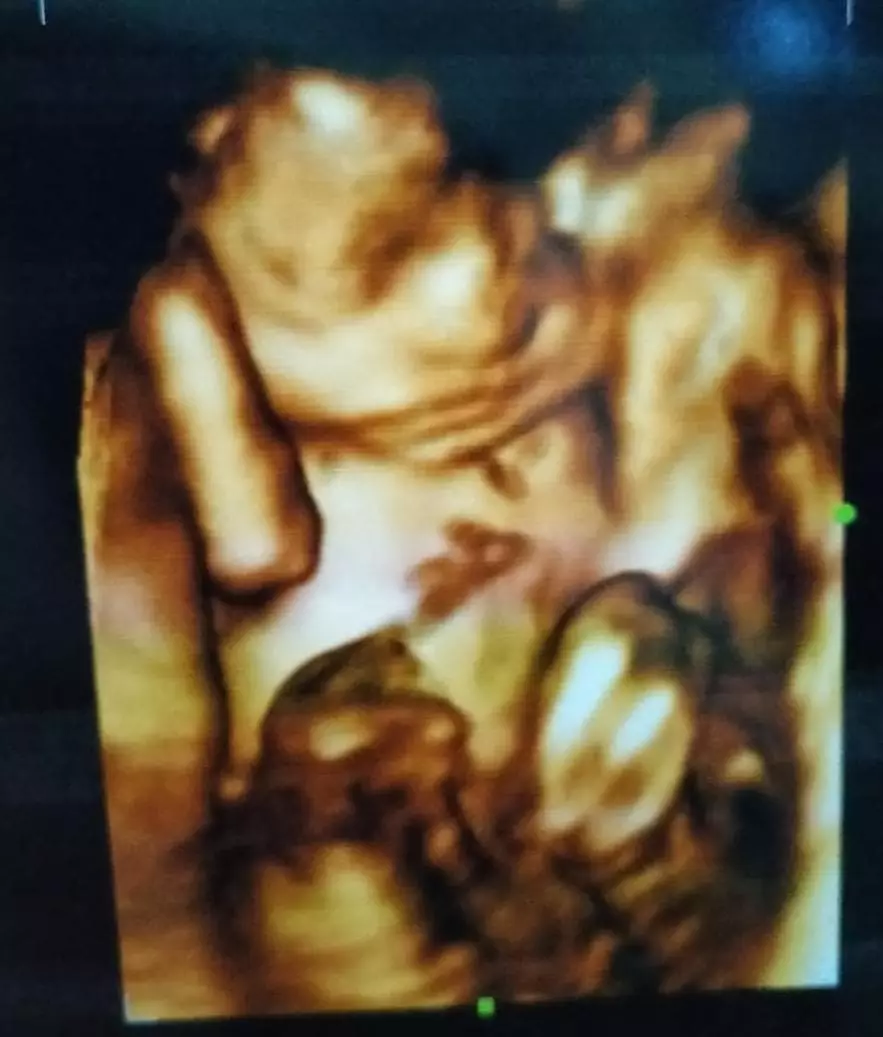

Brilio.net - Istri Rizky D'Academy, Nadya Mustika kini tengah mengandung anak pertamanya. Baru-baru ini ia mengunggah potret hasil USG bayi untuk kedua kalinya. Namun, potret USG kali ini tampak berbeda lantaran wajah sang bayi sudah terlihat.

Hal ini diketahui dari unggahan Instagram Nadya pada Rabu (17/2) kemarin. Dalam foto terlihat cukup jelas wajah bayi. Sang bayi sudah semakin besar, tampak sudah terbentuk bagian tubuhnya mulai dari kepala, leher hingga bagian tangan dan dada.

Dalam keterangan foto, Nadya juga menuliskan ungkapan syukur dan bahagianya melihat hasil USG-nya tersebut. Wanita yang dinikahi Rizki DA pada 17 Juli 2020 ini pun menuturkan jika kini sang bayi sudah berusia 31 minggu.

"Masya Allah tabarakallah, bahagia banget klo mandangin hasil USG ini, happy 31 week utun sayang.. ayooo tebak mirip ummi atau abi nya?" tulis Nadya.